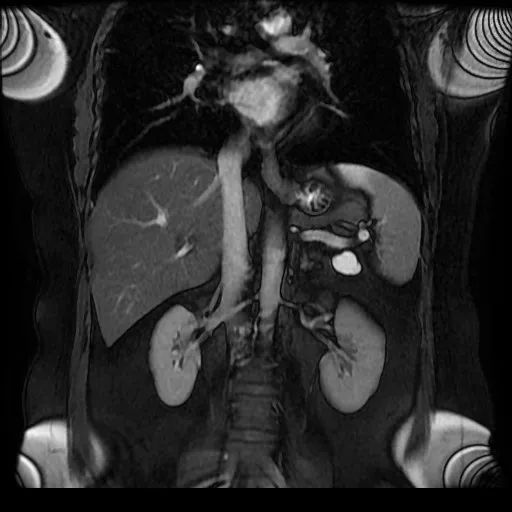

患者刘女士(化名)数月前体检发现胰尾部有一枚肿物,近期就诊上腹部MR增强提示:“胰尾部囊性占位,粘液性囊腺瘤可能”。为进一步治疗,7月27日,患者在家人的陪伴下,赶到广济医院问诊瑞金专家,上海瑞金医院普外科施昱晟教授详细评估后为其制定手术方案。完善术前准备后,施教授专程赴淮,带领东方普外团队顺利完成手术。“从求诊到开刀,专家和先进技术都在淮南解决,免了我们家属奔波之苦,更救了我们家人的命啊!”家属感慨地说。